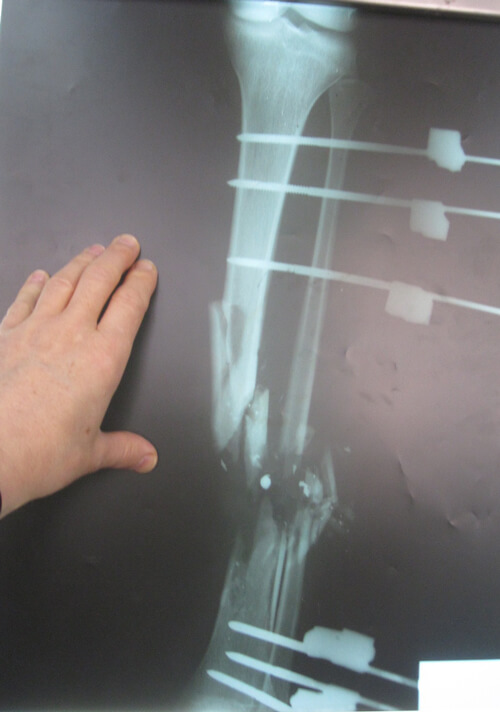

A 17-year-old adolescent sustained a GSW to his right distal leg (medial entrance wound, lateral exit wound) (Figure 7). He had a Gustilo IIIc [5,6] compound fracture (Figure 8). Acutely, the posterior tibial artery was ligated, tissues debrided and an external fixator placed. Two further soft tissue debridements were performed and unfortunately, the medial wound was closed. There was total loss of function in the peroneal and posterior tibial nerves.

Figure 8: X-ray right leg: Gustilo IIIc comminuted, compound fracture

of distal third tibia and fibula with bone gap.